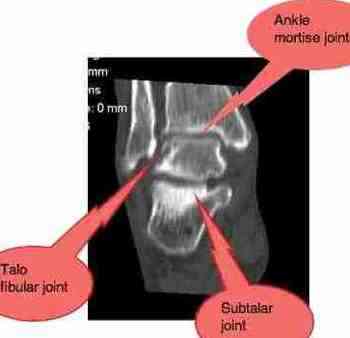

Joining the foot to the lower leg are two joints; the ankle mortise and the subtalar joint. Actually the latter, is a complex of three joints; see our ankle joint pain page.

When subluxated it causes very sharp pain, just as you describe. Normally it responds very quickly to a couple of simple adjustments, unless the cartilage was damaged, or worse a fracture lurking there in the ankle.